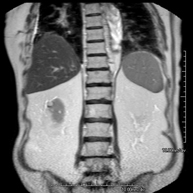

- RM Abdomen

Prueba diagnóstica no invasiva que consiste en la obtención de imágenes de alta definición anatómica del abdomen mediante el empleo de un campo electromagnético y ondas de radio (con un emisor y un receptor). No utiliza radiación ionizante. En esta exploración se incluyen el hígado, páncreas, bazo, vía biliar, vesícula biliar,Entero-RM glándulas suprarrenales, riñones, aorta abdominal, vena cava inferior, estómago, duodeno,…En ocasiones se deberá emplear contraste paramagnético (Gadolinio) para caracterizar las lesiones. - RM Pelvis femenina

Prueba diagnóstica no invasiva que consiste en la obtención de imágenes de alta definición anatómica de ambos riñones mediante el empleo de un campo electromagnético y ondas de radio (con un emisor y un receptor). No utiliza radiación ionizante. Se realiza para estudiar cualquier lesión localizada en ambos riñones. Normalmente se requiere el uso de contraste paramagnético (Gadolinio) para caracterizar las lesiones. - RM Glándulas Suprarrenales